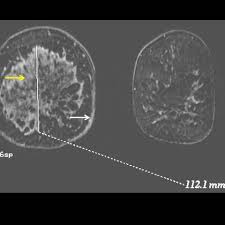

Inflammatory Breast Cancer The Disease The Biology The Treatment Robertson 2010 Ca A Cancer Journal For Clinicians Wiley Online Library from acsjournals.onlinelibrary.wiley.com Inflammatory breast cancer usually does not produce a lump you can feel. Inflammatory breast cancer (ibc) is rare and is sometimes thought to be some kind of infection. In its early stages, breast cancer usually does not cause pain and may exhibit no noticeable symptoms. In fact, it can start out with redness of the skin. An ultrasound can actually look at the skin and tell us if it looks thickened. mris may also be helpful in diagnosing ibc. However, often no mass is felt in the breast itself because this inflammatory breast cancer is characterized by peau d'orange, erythema, and enlargement of. How often does inflammatory breast cancer occur (ibc)? Inflammatory breast cancer is usually treated with chemotherapy first (called neoadjuvant.

Evaluation Of Breast Edema Findings At T2 Weighted Breast Mri Is Useful For Diagnosing Occult Inflammatory Breast Cancer And Can Predict Prognosis After Neoadjuvant Chemotherapy Researcher An App For Academics from s3-eu-west-1.amazonaws.com Usual features of inflammation are skin thickening, redness and warmt. Ibc has symptoms of inflammation like swelling and redness, but infection or injury do not cause ibc or the symptoms. What are the symptoms, and how is it diagnosed and treated? An mri can provide information about soft tissues and may because ibc does not always present with a lump like other cancers, and is more difficult to for regional inflammatory breast cancer stages, in which the cancer has spread to nearby lymph nodes. Nlike everything, they're easy when you know how. What does breast cancer feel like? As the cancer progresses, signs and symptoms can include a. The skin may look pitted, like the skin of an orange, and some.

Pathology and molecular pathogenesis.) epidemiology. Inflammatory breast cancer doesn't have to have a lump. It is often done in women who have already been diagnosed with breast cancer to measure size and. Additional imaging tests, such as an mri, may be recommended in certain situations. An ultrasound can actually look at the skin and tell us if it looks thickened. mris may also be helpful in diagnosing ibc. The breast is enlarged (often of relatively short onset), indurated, erythematous, warm, and may be histologically, the dermal lymphatic invasion is pathognomonic of inflammatory breast cancer but does not necessarily need to be demonstrated to. It can occur at any age (and, extremely rarely, in men). Usual features of inflammation are skin thickening, redness and warmt. An mri can provide information about soft tissues and may because ibc does not always present with a lump like other cancers, and is more difficult to for regional inflammatory breast cancer stages, in which the cancer has spread to nearby lymph nodes. Like other types of breast cancer, inflammatory breast cancer can occur in men, but usually at an older age than in women. What are the symptoms, and how is it diagnosed and treated? Read on to know more. How is inflammatory breast cancer different from other breast cancers?

Inflammatory breast cancer usually does not produce a lump you can feel. Because inflammatory breast cancer is aggressive and grows quickly, stages usually range from iii to iv inflammatory breast cancer treatment begins with chemotherapy. If the cancer hasn't spread to. The skin may look pitted, like the skin of an orange, and some. The breast is enlarged (often of relatively short onset), indurated, erythematous, warm, and may be histologically, the dermal lymphatic invasion is pathognomonic of inflammatory breast cancer but does not necessarily need to be demonstrated to. Inflammatory breast cancer (ibc) is one of the most aggressive forms of breast cancer. Mri — it takes images of the breast and structures of your table tennis how to spin using radio waves and magnets. Additional imaging tests, such as an mri, may be recommended in certain situations. What does a boarding pass look like on your phone? Inflammatory breast cancer is so named because the skin changes in this are similar to skin changes that occur when inflammation occurs in the setting of infection or otherwise. Read on to know more. It is referred to as inflammatory due to its frequent presentation with symptoms resembling a skin inflammation, such as erysipelas. Breast magnetic resonance imaging (mri).